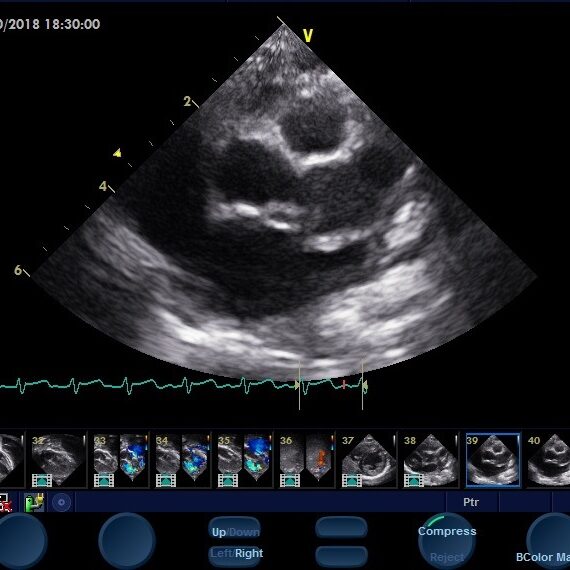

A double quadri in a week! Quadricuspid aortic valve is an extremely rare finding on echocardiography. The incidence is 0.0059-0.0065% for patients undergoing transthoracic echocardiographic examinations. Presenting two successive cases seen in two successive weeks in our echo lab! Your browser does not support the video tag. Your browser does not support the video tag.…